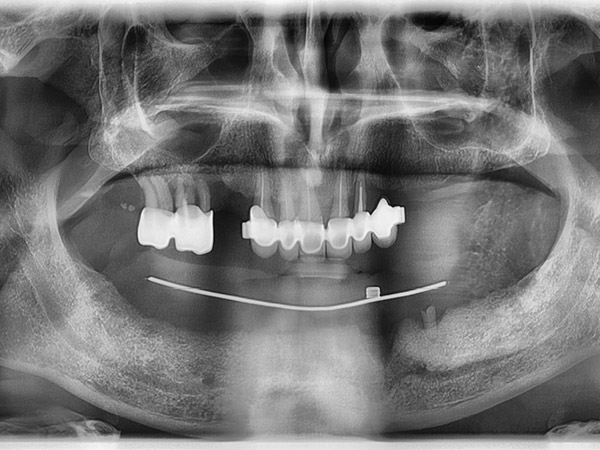

Sono state eseguite Tac con dima radiologica e progettazione per inserimento implantare tramite dima chirurgica di sei impianti AZ Implant tipo DX con overdenture a carico immediato.